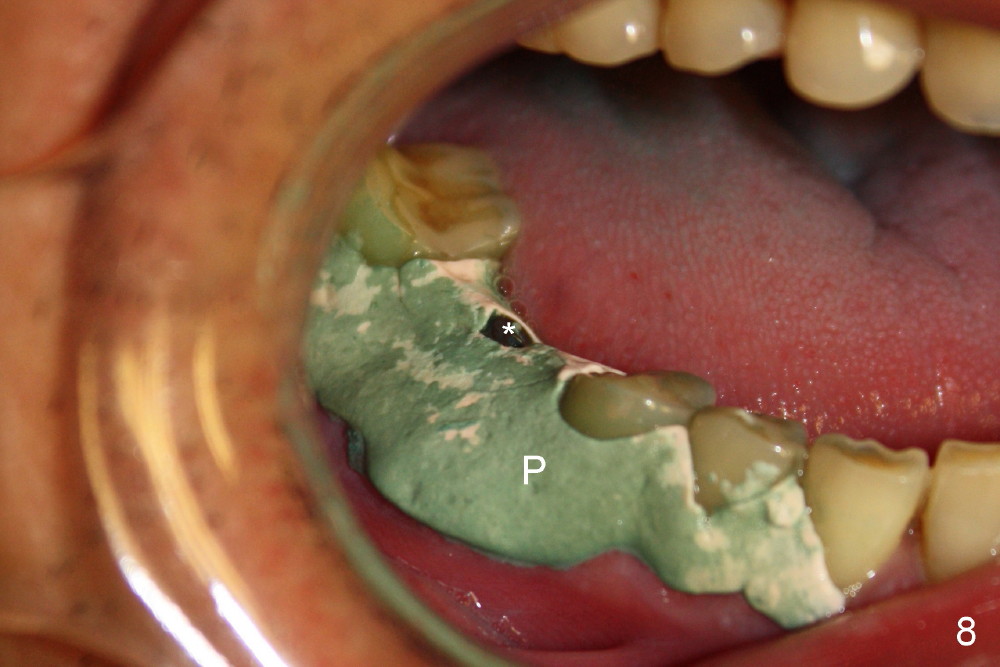

As to where to place an implant, we try to engage the largest tap (8 mm in diameter) into the mesial socket without binding. The buccal plate of the mesial socket is missing.  It is risky to extend osteotomy in the mesial socket.  Besides, the septum (Fig. 4 S) is not as tall as the distal socket (D).  It appears that the distal socket is the safest place to place an implant.  Furthermore, no drill is used for distal osteotomy.  Instead two osteotomes (3.5x15 and 4x15 mm tapered osteotomes) are used to expand the distal socket with intention to push the septum mesially.  Since the bone density is high, the osteotomes seem not to work as effectively as expected.  Then a 4.5x17 mm tap is placed at the depth ~ 14 mm with stability (Fig.5).  Finally a 5x14 mm tissue-level implant is placed with insertion torque >60 Ncm (Fig.6).  Allograft is placed in the mesial socket and buccal aspect of the distal socket, followed by insertion of collagen plug and membrane (Fig.7).  After insertion of an abutment (Fig.8 (taken 6 days postop) *), perio dressing (P) is applied to cover the wound.  There is no postop paresthesia.